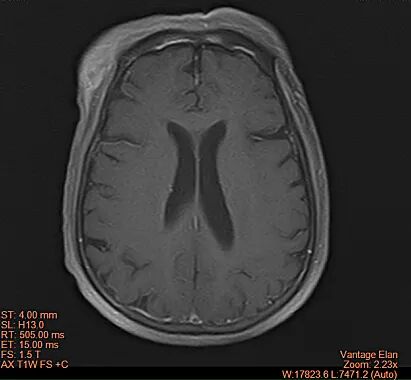

治疗后

治疗后(影像图)